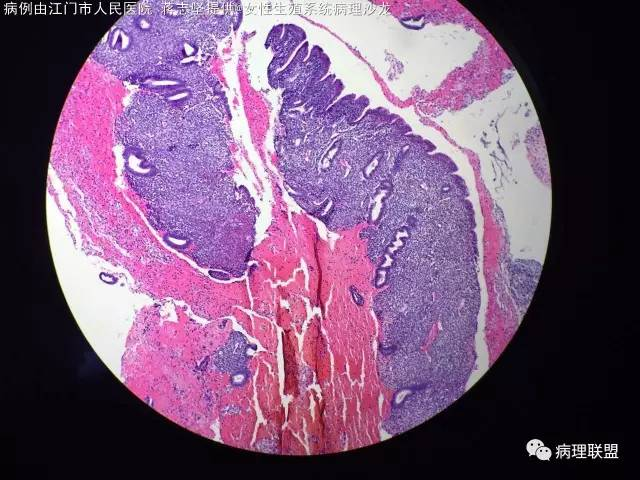

女,20岁,宫腔赘生物,子宫下段后壁2×1×1cm,HCG 不高,一年前卵巢手术,病理,浆液性囊性腺纤维瘤,本次宫腔镜手术(病例由江门市人民医院 蒋志坚提供,致谢!)